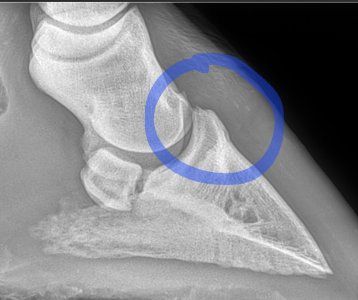

We are going to confer in Monday to see how he is with a view to her coming back if not sound. Options are possible coffin joint arthritis although I'd asked her if she thought it was this before when she came out initially to xray and she said she felt the xray wasn't bad enough for it to be this. Xray attached.

Second photo heel area.

I'm not sure I'd be happy with this area here B. That channel looks like it narrows and also looks like it's forcing the joint apart further back. I'm no expert at xrays though. Ludo and Charlie below for comparison I'm sorry Lari is continuing to cause you worries.

What I'm struggling with, is that the vet who took the xrays did not make any comment about the area ringed in ycbm post. If I were you @Birker2020 I would see if you can get the xrays reviewed by another vet, and in particular question them about the highlighted area.

Don't understand as when the vet took the xrays she specifically said no ringbone or sidebone, no navicular, or rotation.

Don't think the two bones should be touching

That first xray the circle area is too close together

From where YCBM has circled the bones deffo look to be touching, potentially rubbing and therefore could be the cause of the mystery lameness - I had my scaphoid bone in my right wrist rubbing against other bones in close proximity from a prior riding accident where it didn't heal quite right, and until surgery, I had days where I couldn't use my hand first thing but it would loosen up throughout the day and we couldn't figure out what was causing it, till we blocked the area and a comparison before and after was done. I was also in a heck of a lot of pain and general pain relief (paracetamol and ibuprofen) wouldn't touch it - I was on hospital prescribed drugs and even then it was the higher dose that required me to be tapered off slowly.

May 23 to March 25, the difference is very clear. Sorry B, even if that isn't the cause of the current lameness you've got a definite issue there. I would personally be particularly worried about how and why the joint is being pushed apart in the middle.

Not from what I can see and from what I see on other x rays of good joints. The joint space shouldn't, I don't think, have got bigger in the middle like that and the culprit looks like arthritis at the front, commonly called low ringbone.